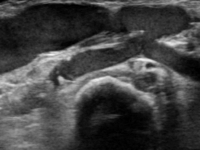

・静脈系の観察

吻合部から中枢へ向かって走査し、血管の走行や太さ、血管までの深さ、狭窄や石灰化、血栓等の有無を観察しています。長軸断面、短軸断面それぞれで観察し、また、カラードプラも使用しできるだけ正確に、血管内の状況を把握するようにしています。